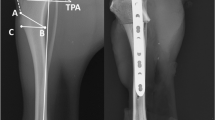

To ascertain PF kinematics, a 3D–to-2D image registration process was used to combine 3-dimensional bone model data with 2-dimensional fluoroscopic data from 3 representative gait cycles that best caught the entire gait cycle encompassed within the fluoroscopic field of view. The digital bone models of the patella and femur were superimposed over the fluoroscopic images and their projected silhouettes were translated and rotated such that the contours precisely matched the corresponding contours of the fluoroscopic imagesFootnote 5, as previously described (Fig. 2) [23]. The patella was positioned centrally within the trochlear groove, such that the articulating surface of the patella at the center of the patella remained as congruent as possible with the trochlear groove in the axial plane. The output of the software represents the individual model positions in space, and these results were converted to the relative positions of the bone models to each other using a custom computer programFootnote 6.